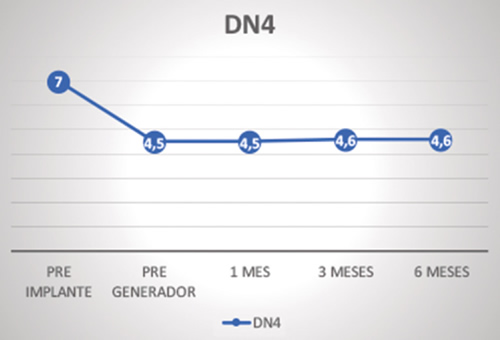

El número de descriptores de dolor neuropático de la escala DN4, respecto al valor basal (7 ± 1,3), solo disminuyó de forma significativa a los 6 meses (4,6 ± 2,6; p = 0,034), mostrando una tendencia a la significación en las valoraciones a 2 semanas (4,5 ± 3,4; p = 0,083), 1 mes (4,5 ± 3,8; p = 0,086) y 3 meses (4,6 ± 3; p = 0,062) (Figura 5). Nueve de los diez pacientes tenían inicialmente alodinia patente y en todos los implantados hubo una disminución o desaparición total de esta.

Fig. 5. Número de palabras elegidas en el DN4